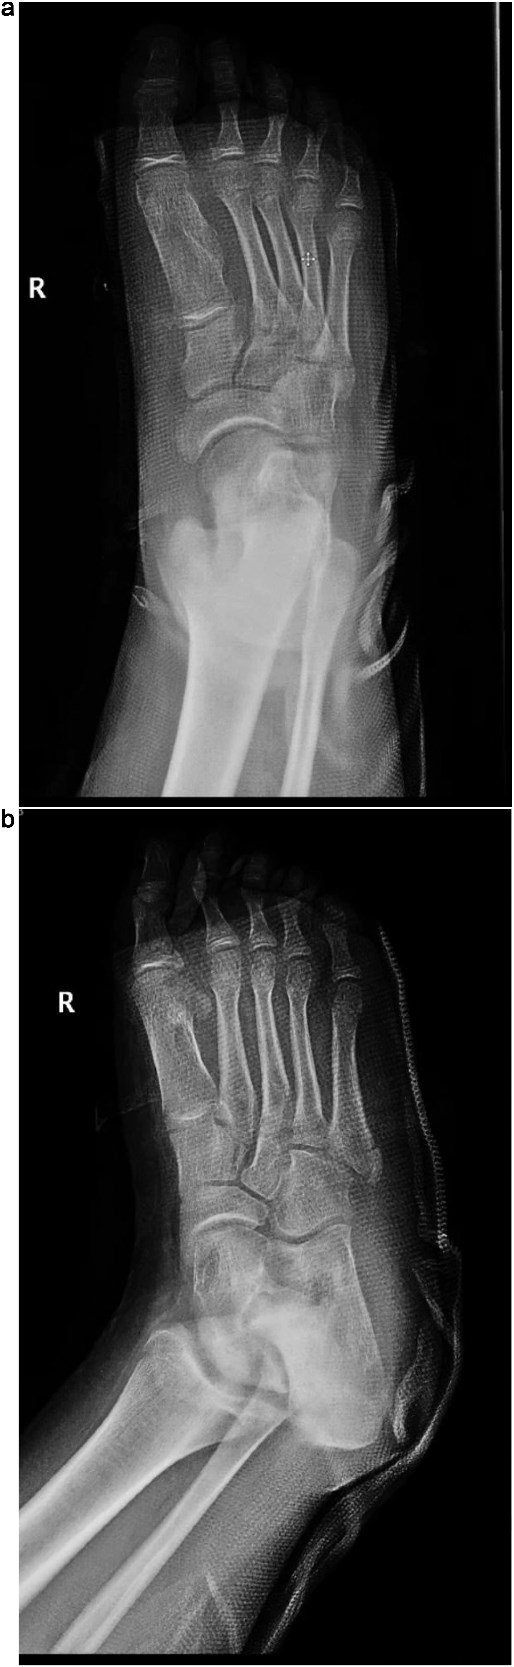

The patient was placed in the supine position for surgery. Under general anesthesia, a dorsal incision over the first metatarsal with proximal extension to the medial cuneiform was made. The subcutaneous layers were then dissected. The interval between the extensor hallucis longus and extensor hallucis brevis was identified. An exostosis extending from the medial aspect of the medial cuneiform to the medial side of the first metatarsal was identified, and its edges were defined. Resection was performed using a power saw. The Lisfranc joint was examined using dynamic testing and was deemed stable. Bone wax was applied to the resection sites, and the subcutaneous layers were approximated, followed by wound closure and dressing. Subsequently, a short back slab was applied. Postoperative radiographs are shown in Fig. 3. Postoperatively, the patient had an excellent functional outcome and was ambulating well during his routine surveillance follow-up visits at 3, 6, and 9 months.

(a) Postoperative anteroposterior radiograph of the right foot demonstrating complete resection of the intermetatarsal lesion and normalization of the intermetatarsal spacing. (b) Oblique postoperative view confirming successful removal of the mass with preserved alignment of the first metatarsal and surrounding structures.